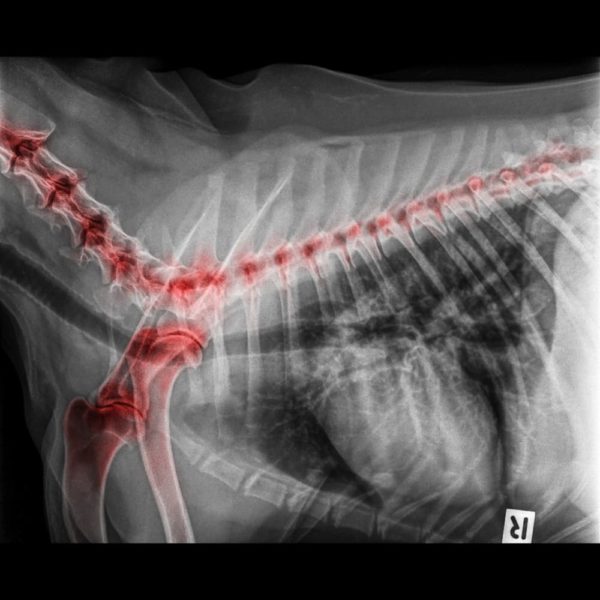

Common side effects of Galliprant in dogs include vomiting, diarrhea, decreased appetite, and lethargy Galliprant is a non-steroidal anti-inflammatory drug (NSAID) prescribed by veterinarians to treat pain and inflammation related to osteoarthritis in dogs The dosage structure recommended by the manufacturer is: 8 to 15 lbs.—½ of a 20 mg tablet; 15.1 to 30 lbs.—1 full 20 mg tablet; 30.1 to 45 lbs.—½ of a 60 mg tablet

Is Your Dog Suffering from Osteoarthritis? Allivet Pet Care Blog. What Happens if My Dog Consumes More Galliprant Than the Recommended Dose? Just like overindulging in a tasty treat can lead to tummy troubles, consuming too much Galliprant can adversely affect your dog's well-being too Galliprant is a non-steroidal anti-inflammatory drug (NSAID) prescribed by veterinarians to treat pain and inflammation related to osteoarthritis in dogs